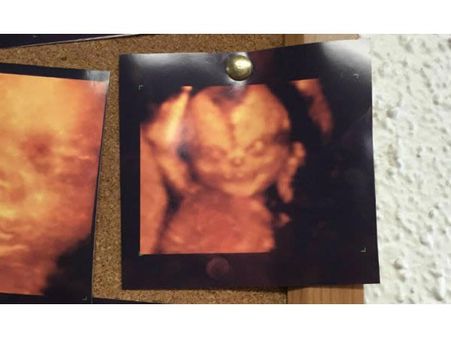

The Parents Who Were Scared With A Creepy Face

When the parents went in to get the wife's weekly checkup done, they found a creepy red, leering demon-looking face. This was the image that was got when the couple went in for a "4D" ultrasound scan.